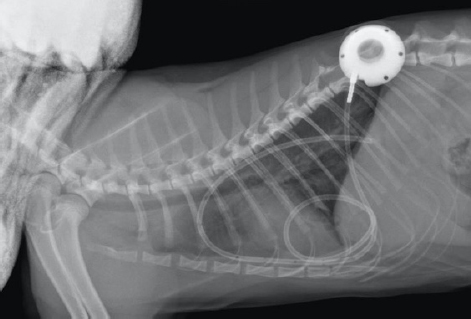

The cat was premedicated with methadone (Methone, Ceva Animal Health, Glenorie, Australia) 0.3 mg/kg IV, induced with alfaxalone (Alfaxan, Jurox Animal health, Crawley, UK) 1 mg/kg IV to effect and maintained under general anesthetic with isoflurane and oxygen. A right-side approach to the thoracic wall was elected based on the ultrasonographic distribution of the pleural effusion. A 4-cm skin incision was made in the dorsal 3rd of the chest wall at approximately the 10th intercostal space, tunneling to a second incision in the 8–9th intercostal space of the central chest area. An 18-gauge catheter and a 0.035″ J-tipped guide wire were then introduced. An eight French expander was used over the J-wire, and a seven French round tip fenestrated silicone tube was placed and secured with suture material in surrounding soft tissue around the thoracostomy tube entry site. The port was secured in the dorsal site with sutures to the fascia of the latissimus dorsi. Port patency was verified using a Huber point needle before and after skin closure. The skin closure was caudal to the port so that the incision line would not interfere with drainage and the healing of the skin would be favorable. Thoracocentesis and lavage of the pleural space were carried out before the surgical site’s closure with 250 ml of warmed sterile saline solution (0.9% NaCl, Baxter Healthcare Corp, Deerfield, IL). An esophagostomy tube was placed following the pleural port placement. Radiographs showed satisfactory positioning of the pleural port (Fig. 4). Lavage and drainage of the pleural space were successfully carried out following surgery using 50 ml of sterile saline solution q12 hours without complications.

Fig. 4. Day 6: left lateral view of thorax showing placement of a pleural port device with partial resolution of pyothorax.